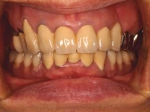

両側5歯症例

両側5歯症例両側5歯症例両側5歯症例 主訴-義歯のバネが壊れて手前の歯が痛んできた。 術前(旧義歯装着、鏡像) 術前(下顎粘膜面、鏡像)術前(下顎粘膜面、鏡像)術前(下顎粘膜面、鏡像) 術前レントゲン術前レントゲン術前レントゲン 術前口腔内(正面観)術前口腔内(正面観)術前口腔内(正面観)

術後(鏡像)術後(鏡像)術後(鏡像) 術後口腔内(正面観)術後口腔内(正面観)術後口腔内(正面観)もう入れ歯は要らなくなりました。 術後レントゲン術後レントゲン術後レントゲン